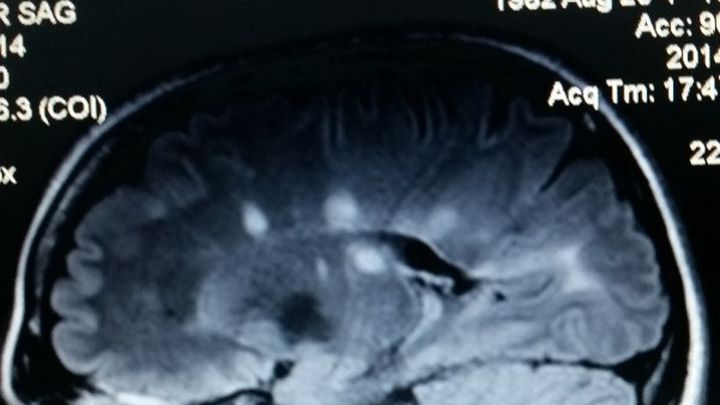

As you may know, I've been battling MS for almost 10 years. MS is a chronic disabling auto immune disease that effects the central nervous system.. Ie. The brain and spinal cord. Currently I am in a relapse/remitting phase (aka :rrms) Meaning that there's periods of time in which my disease worsens and then gets better with treatment.

As you may know, I've been battling MS for almost 10 years. MS is a chronic disabling auto immune disease that effects the central nervous system.. Ie. The brain and spinal cord. Currently I am in a relapse/remitting phase (aka :rrms) Meaning that there's periods of time in which my disease worsens and then gets better with treatment.